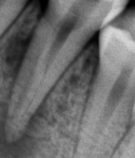

В стоматологической клинике "5 Принципов" в Симферополе мы гордимся тем, что каждый пациент получает индивидуальный подход и безупречный результат в области эндодонтического лечения под микроскопом. Наши специалисты применяют современные цифровые технологии, микропроцессорные и нейромодуляционные инструменты, что позволяет достичь максимальной точности и минимального дискомфорта. В портфолио клиники — широкий спектр кейсов: от первичной диагностики пульпита до сложной ретенированной резорбции и повторной эндодонтии. Мы беремся за зубы любых степеней сложности: от моляра до резцов, используя щадящие концевые инструменты и безболезненные методы постоянной анестезии. Все процедуры проходят под увеличением, что обеспечивает точное удаление инфицированной ткани и сохранение естественной анатомии зуба.Особое внимание мы уделяем постпроцедурному наблюдению: контроль за герметичностью заполнения корневых каналов, профилактические рекомендации и возможная корректировка плана лечения при необходимости. В "5 Принципах" мы разумно сочетаем комфорт, эстетическую привлекательность и долгосрочную функциональность. Результат — здоровые зубы, уверенная улыбка и спокойствие наших пациентов в Симферополе. Запишитесь на консультацию и убедитесь сами в нашем подходе к качественному эндодонтическому лечению.